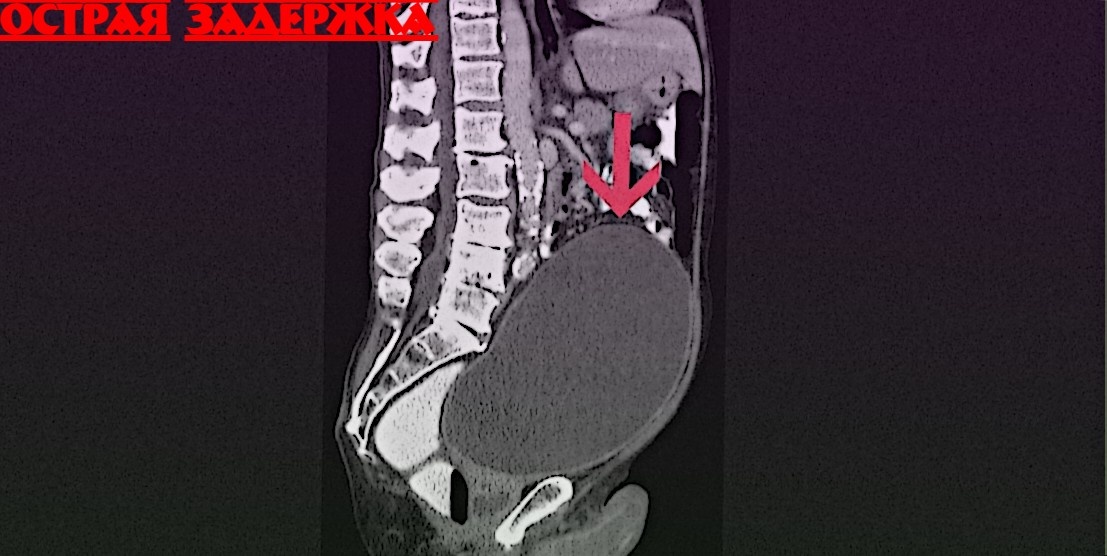

Острое мочевое задержание — это состояние, при котором человек не в состоянии произвести мочеиспускание, несмотря на полное переполнение мочевого пузыря. Это может быть болезненно и опасно для здоровья.

Острое задержка мочи может возникнуть по различным причинам, включая:

Увеличение предстательной железы (аденома)

Острая инфекция мочевыводящих путей

Узкая уретра

Травмы или операции в области таза